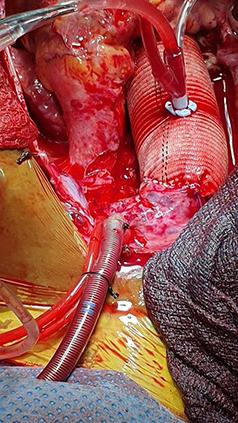

资源有限地区由当地医生实施心脏手术:来自埃塞俄比亚的经验。

Heart surgery by the locals in resource-limited settings: The experience from Ethiopia.

In developing countries, despite its demand is high, heart surgery is not always accessible to the neediest patients. We aimed to describe the early outcomes of heart surgeries that were performed by a local cardiac surgical team in Addis Ababa, Ethiopia.

A total of 290 patients who underwent heart surgery during the specified period were included in the study. Of the total, 192 patients underwent valve surgery (177 were patients with rheumatic valvular disease and 15 were valve surgeries with other causes) with a 30-day mortality rate of 9 (4.7%), 33 patients underwent coronary artery bypass graft with a 30-day mortality rate of 3 (9.1%), 58 patients underwent repair for congenital heart diseases with no 30-day mortality. Specifically, button Bentall was done for 1 patient; maze procedure was done for 2 patients along with mitral valve surgery, and a total of 7 out of 290 (2.4%) underwent redo heart surgery. The overall procedure-related mortality was 4.1%.

CONCLUSIONS